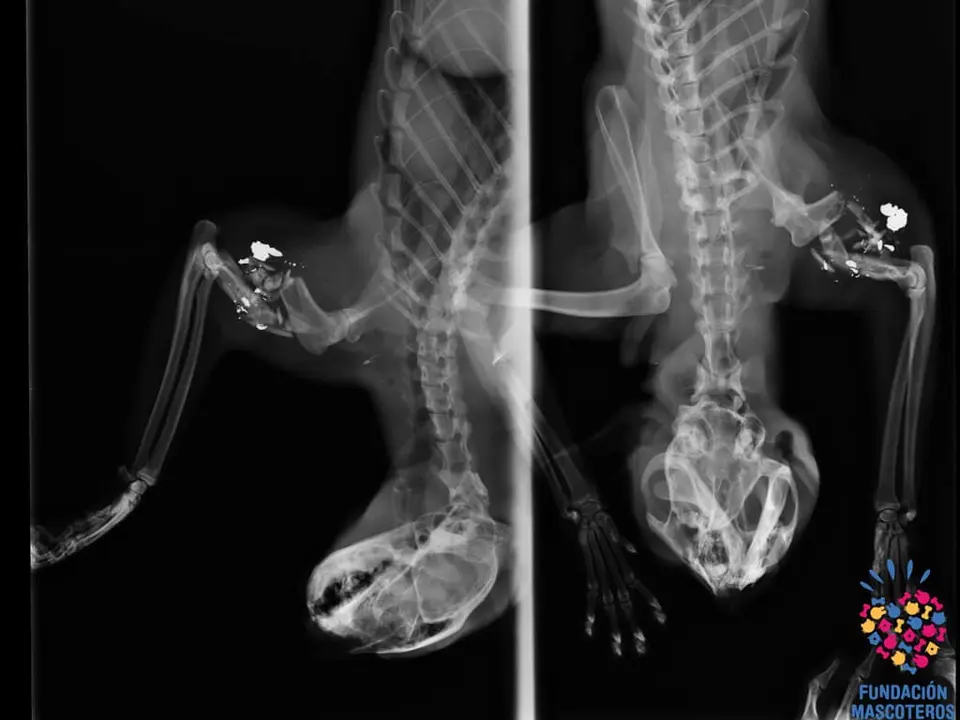

La sorpresa fue cuando al hacerle una radiografía observaron que tenía completamente destrozado el húmero de una de sus patas delanteras por una bala.

Al dormirle, además pudieron comprobar que el proyectil también le había impactado en el cuello.

La cirugía duró dos horas y media y consistió en la limpieza de la zona del material óseo, los restos de bala, la instalación de aguja, placa y 6 tornillos.